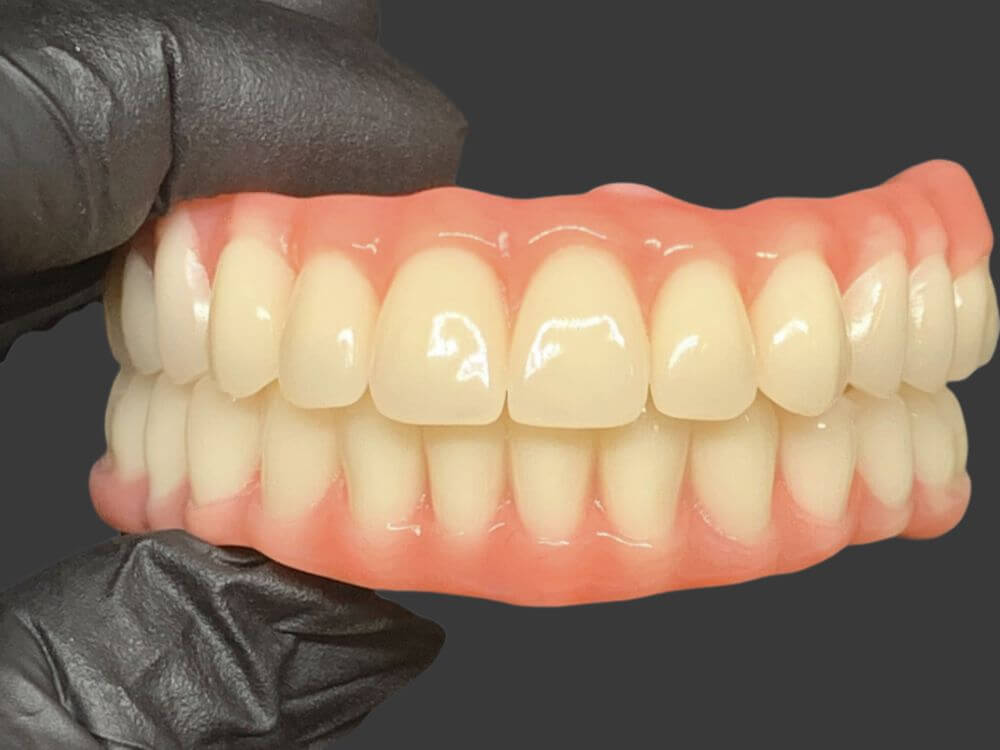

Com apenas 4 implantes é possível instalar uma prótese fixa com todos os dentes da arcada. Não necessita enxerto ósseo. Solução rápida e altamente eficaz.

Uma prótese total fixa sobre implantes para quem perdeu todos os dentes de uma arcada. Recupera a força na mastigação e elimina desconforto ao falar e mastigar.